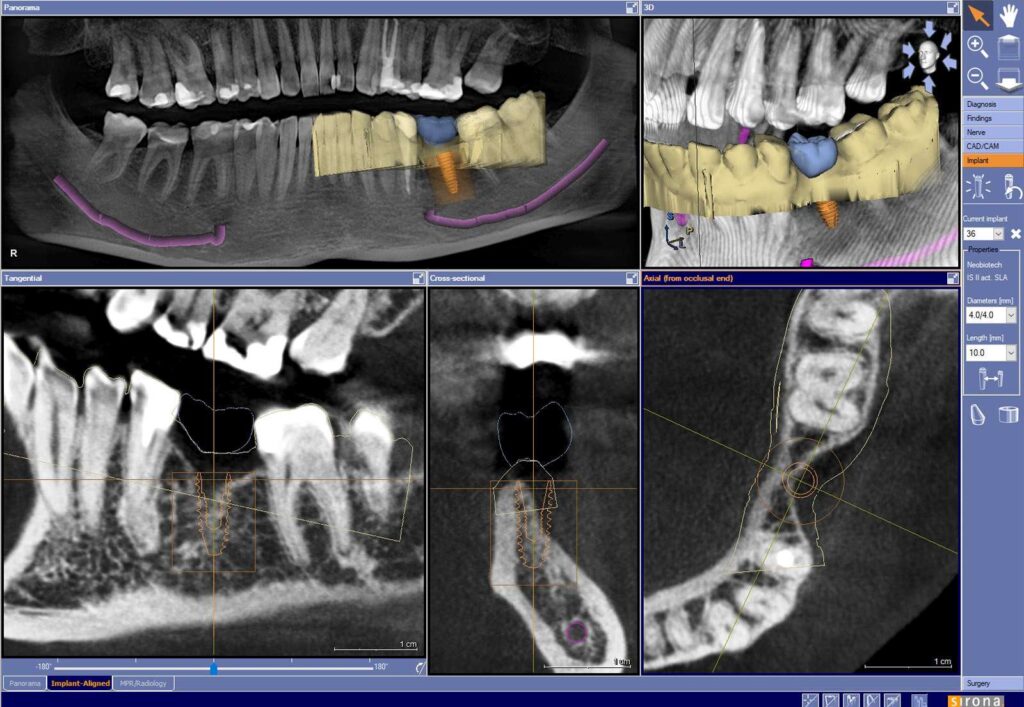

Podczas zabiegów implantacyjnych wykorzystujemy szablony chirurgiczne – komputerowo nawigowana implantologia.

Zadaniem szablonów jest precyzyjne prowadzenie narzędzi chirurgicznych w określonym miejscu i pod określonym kątem. Narzędzia przygotowywane są na podstawie planu przedoperacyjnego. Każdy szablon jest niepowtarzalny i pasuje tylko do jednego pacjenta.

Zalety wykorzystania szablonów podczas nawigowanej implantologii to między innymi:

– znaczne skrócenie zabiegu,

– umiejscowienie implantu w kości z dokładnością do dziesiątych części milimetra,

– możliwość jednoczasowego osadzenia odbudowy protetycznej,

– brak „cięć” w jamie ustnej w celu uwidocznienia miejsca implantacji.